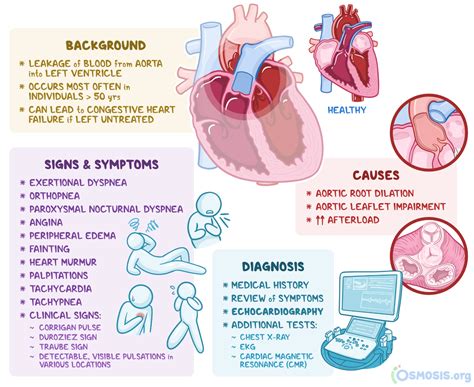

aortic regurgitation murmur

early, decrescendo diastolic murmur that begins right after A2

high pitched, blowing; best heard along left sternal border at 3/4th intercostal spaces with pt sitting up & leaning forward while holding breath in full expiration